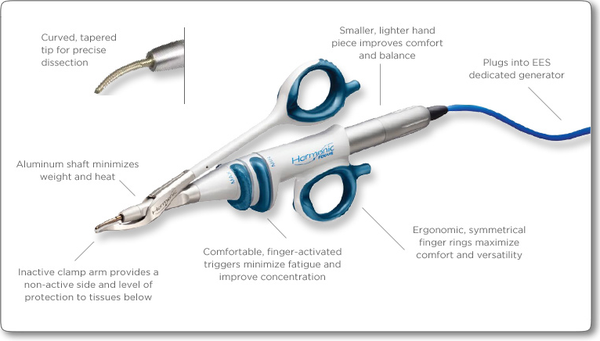

폴동물병원 수술은 반려견과 반려견 수술시 조직 손상을 최소화 하고 빠른 회복을 도울 수 있는 지혈, 결찰을 위한 최신 장비인 Harmonic Scalpel(하모닉스카펠)을 도입하였습니다분당 24시 폴동물병원에서는 독립된 수술공간에서 멸균된 수술기구로 대부분의 수술을 호흡마취를 통해 시행하고 있습니다.또한 세분화된 진통 프로토콜로 통증에 각별한 주의를 기울이고 있습니다.*모든 시술은 예약제로 진행되며 미리 충분한 설명과 상담 후에 진행됩니다.